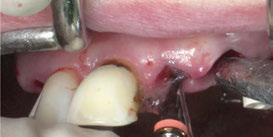

Para ilustrar el proceso, presentamos el caso de una mujer joven diagnosticada de carcinoma adenoide quístico en la región posterior del hemipaladar izquierdo (Figuras 1 y 2). El procedimiento quirúrgico realizado fue una

maxilectomía parcial que incluyó las piezas 24-26 y desde el reborde alveolar hasta la base del cráneo (Figuras 3 y 4). En este caso, la órbita y el globo ocular pudieron ser preservados. La reconstrucción inmediata se realizó mediante un colgajo de músculo temporal homolateral (Figura 5) y el defecto de la fosa temporal fue cubierto mediante una malla de titanio. Posteriormente, la paciente recibió radioterapia (Figuras 6 y 7). 2 años más tarde se diseñó un IS con anclaje en el arbotante nasomaxilar, zona subnasal izquierda

Figura 3. Maxilectomía parcial.

Figura 4. Defecto maxilar tras resección del tumor.